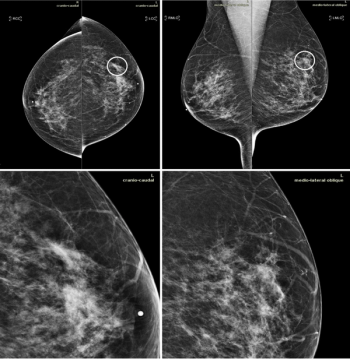

Conducting screening mammography on men with a genetic risk for breast cancer can increase early detection, but clinical guidance and recommendations remain inconsistent.

Screening mammography begins to reduce breast cancer mortality at an age earlier than when most women begin screening.

MRI catches more malignant lesions in women with dense breasts who undergo digital breast tomosynthesis than those who have digital mammography alone.